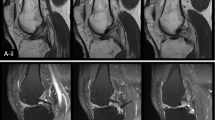

In our qualitative analysis, the shape and signal intensity of the LTL proximal zone, and the direction of high-signal-intensity direction inside the proximal zone were evaluated by consensus of two muskuloskeletal radiologists (HY, TU) using a 2D GRE sequence. The shape of the LTL proximal zone was classified into five types (type 1: regular triangle, type 2: broad-based triangle, type 3: narrow-based triangle, type 4: asymmetrical triangle, and type5: bar shape; Fig. 1). Our study chose the slice in which the largest triangle was found, and signal characteristics in the proximal LTL were evaluated in the same slice. The signal intensity of the LTL proximal zone was classified into three types (type 1: homogeneously low intensity, type 2: linear intermediate or high signal intensity traversing the distal surface, and type 3: linear intermediate or high intensity traversing both proximal and distal surfaces; Fig. 2) [6]. Among type 2 and type 3 signal intensities, the direction of intermediate or high signal intensity inside the proximal zone was classified into five types (type 1: radius–radius (RR) pattern, type 2: radius–ulna (RU) pattern, type 3: ulna–radius (UR) pattern, type 4: ulna–ulna (UU) pattern, and type 5: center (c) pattern) (Figs. 3 and 4). The RR pattern indicated high signal intensity traversing the radial side of the distal surface toward the radial side of the proximal surface, and the RU pattern indicated high signal intensity traversing the radial side of the distal surface toward the ulnar side of the proximal surface. The center pattern shows high signal intensity traversing the center of the proximal zone. The Mann-Whitney U-test was used to determine the significance of the differences in ages among analyzed groups. In each analysis, a P value of ≤0.05 was considered significant.

Drawing shows classifications for proximal LTL signal intensity; a type 1=homogeneously low intensity, b type 2=linear intermediate or high signal intensity traversing the distal surface, and c type 3=linear intermediate or high intensity traversing both proximal and distal surfaces. High-resolution MR images with a microscopy coil show corresponding signal intensity type; d=type 1, e=type 2, and f=type 3